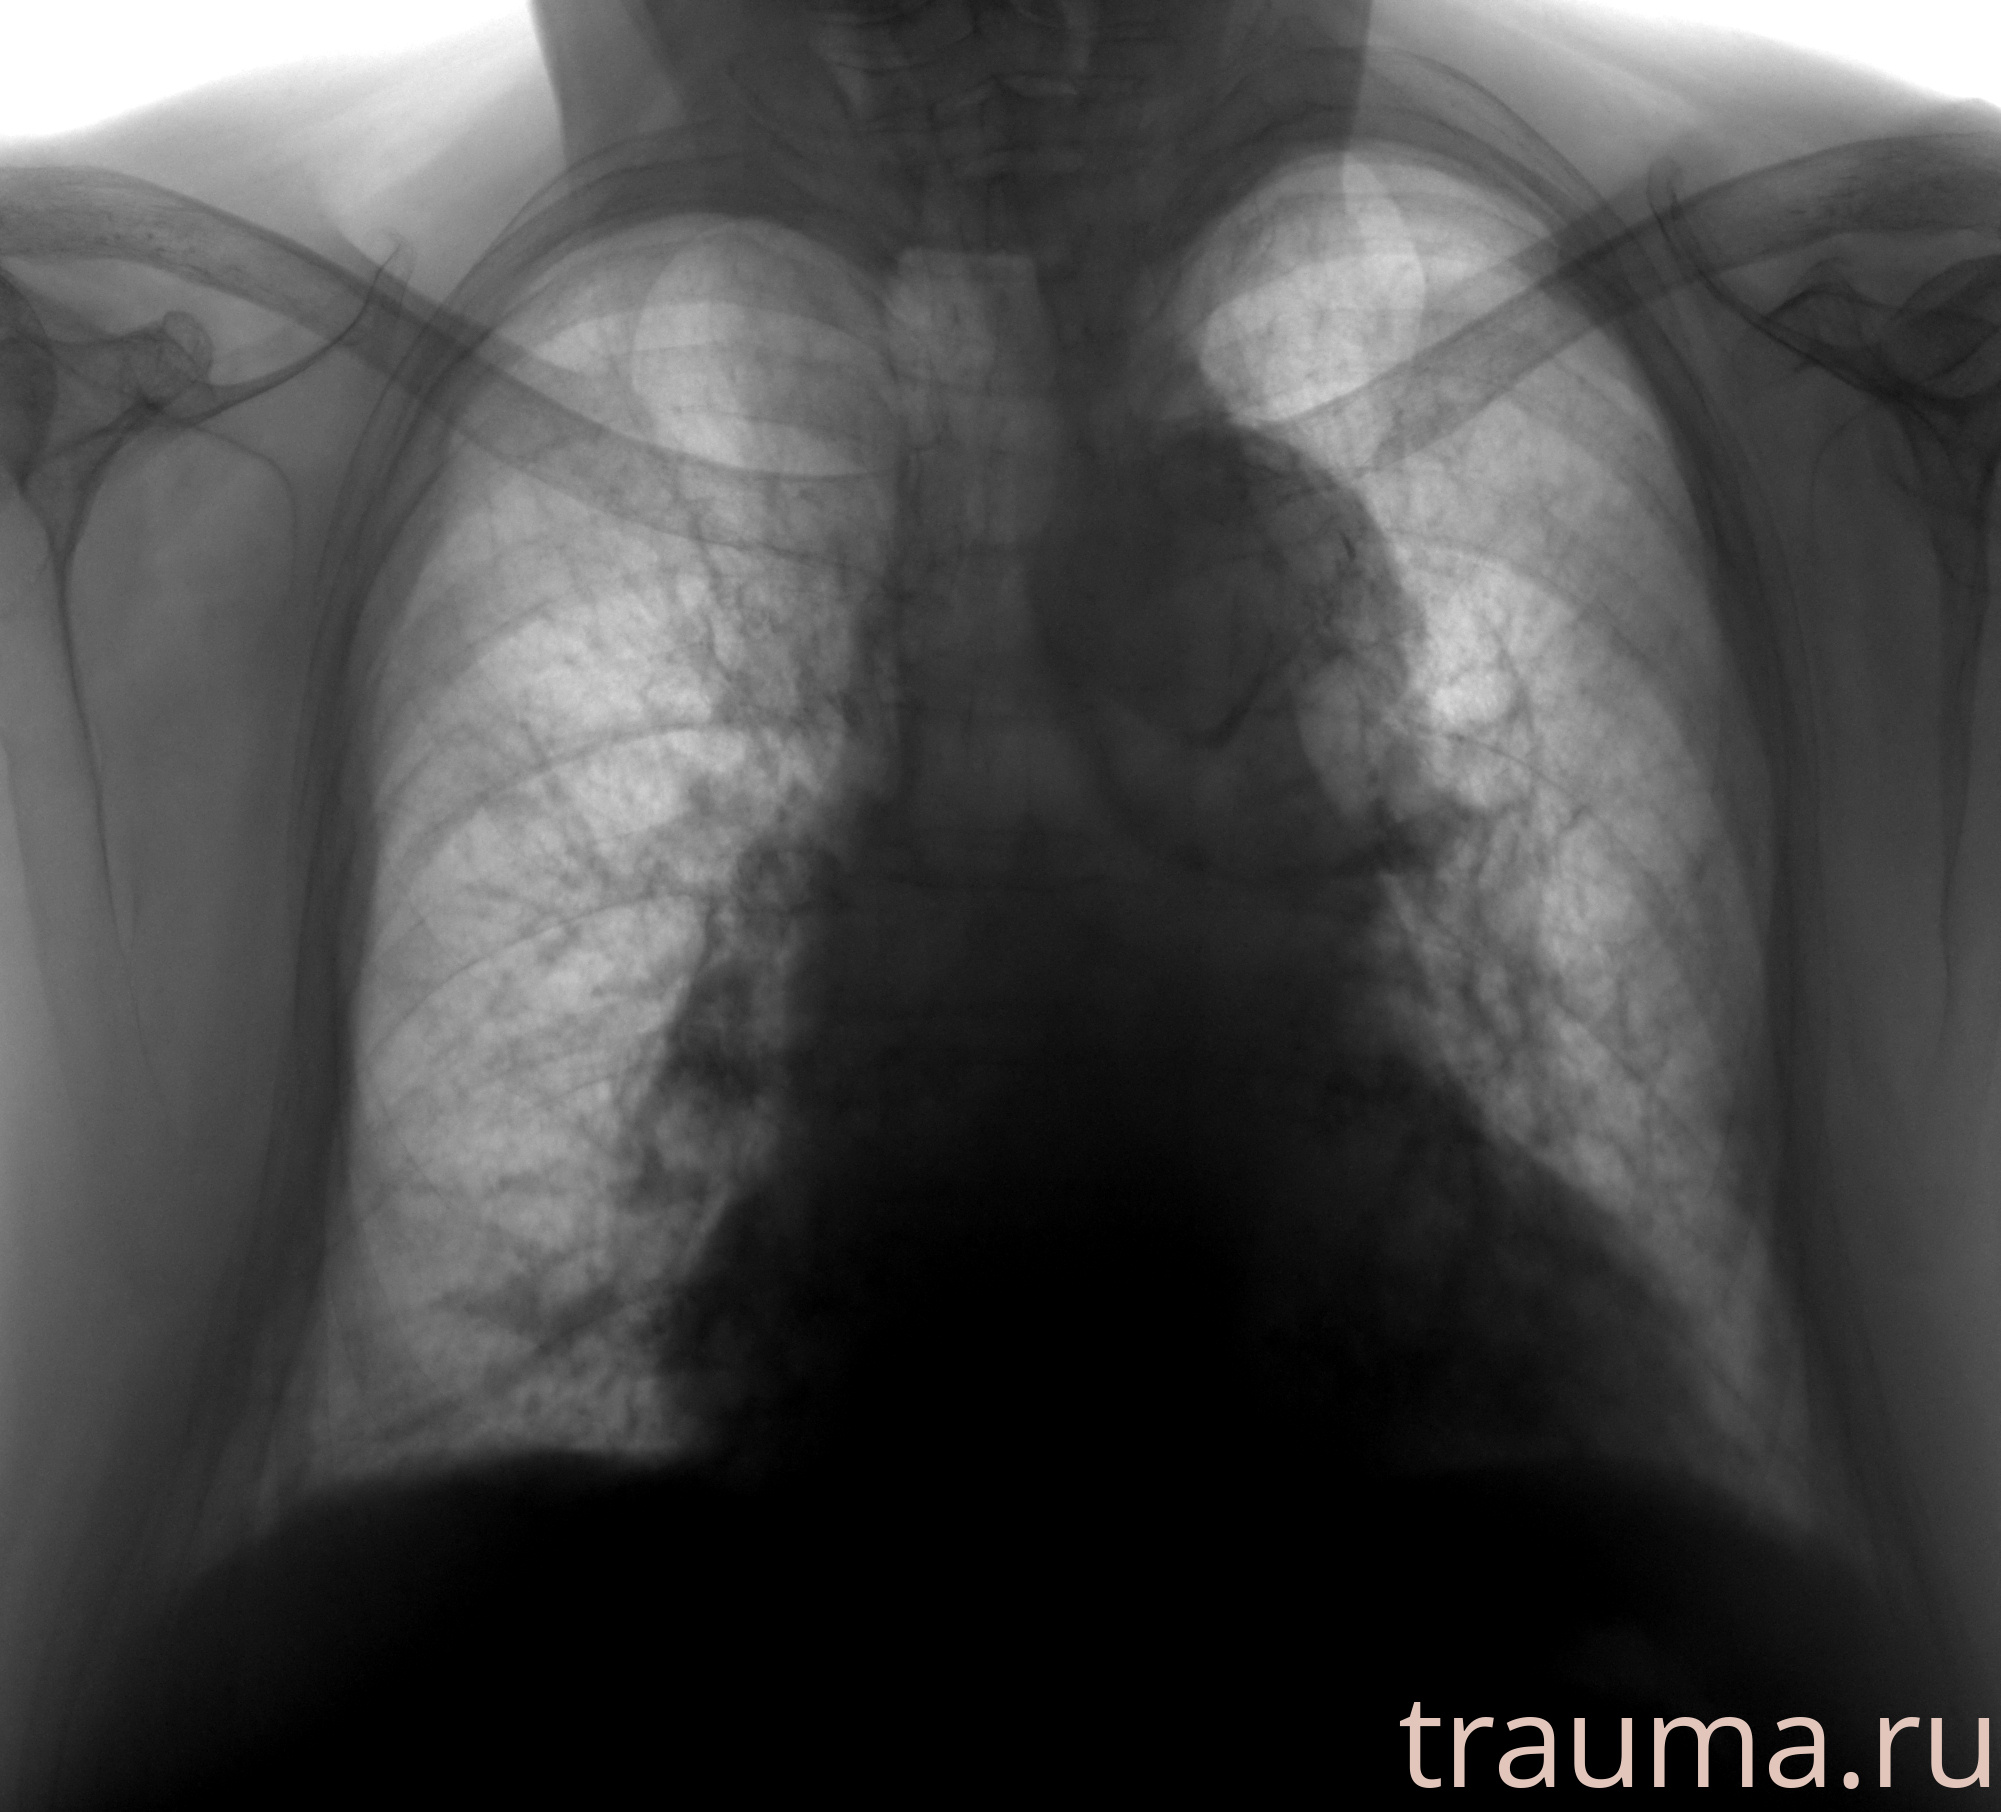

Рентген на дому: по вашему адресу приезжает врач-рентгенолог, травматолог-ортопед с мобильным рентгеновским аппаратом, проводит диагностику травмы или заболевания, делает необходимые рентгенограммы, дает рекомендации по дальнейшему лечению. Получить качественные снимки в домашних условиях возможно благодаря уникальной методике, разработанной МосРентген Центром для института  Склифосовского

при переломе шейки бедра и пневмонии от компании МосРентген Центр - партнера Института имени Склифосовского